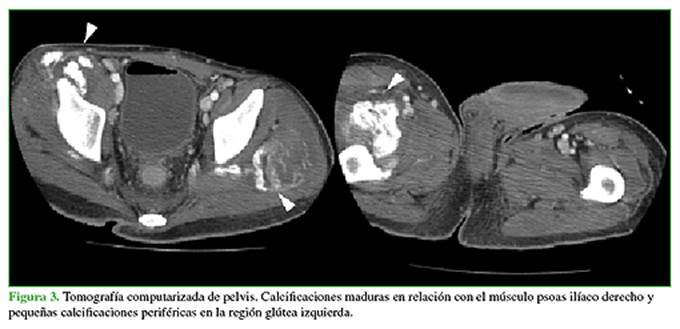

En las radiografías de frente, de ambas caderas, se observa un aumento de la densidad en las regiones glúteas derecha e izquierda. También se reconocen calcificaciones en relación con el trocánter menor derecho (Figura 1).

La resonancia magnética con medio de contraste muestra, en las secuencias, pequeñas imágenes de baja señal en el trocánter menor derecho, leve refuerzo poscontraste. Hay un discreto edema en las secuencias T2. En la región glútea izquierda, la señal en la secuencia T1 es intermedia y, en la secuencia T2, es alta, con marcado refuerzo del medio de contraste (Figura 2). La tomografía computarizada revela calcificaciones maduras en relación con el músculo psoas ilíaco derecho y pequeñas calcificaciones periféricas en la región glútea izquierda (Figura 3).